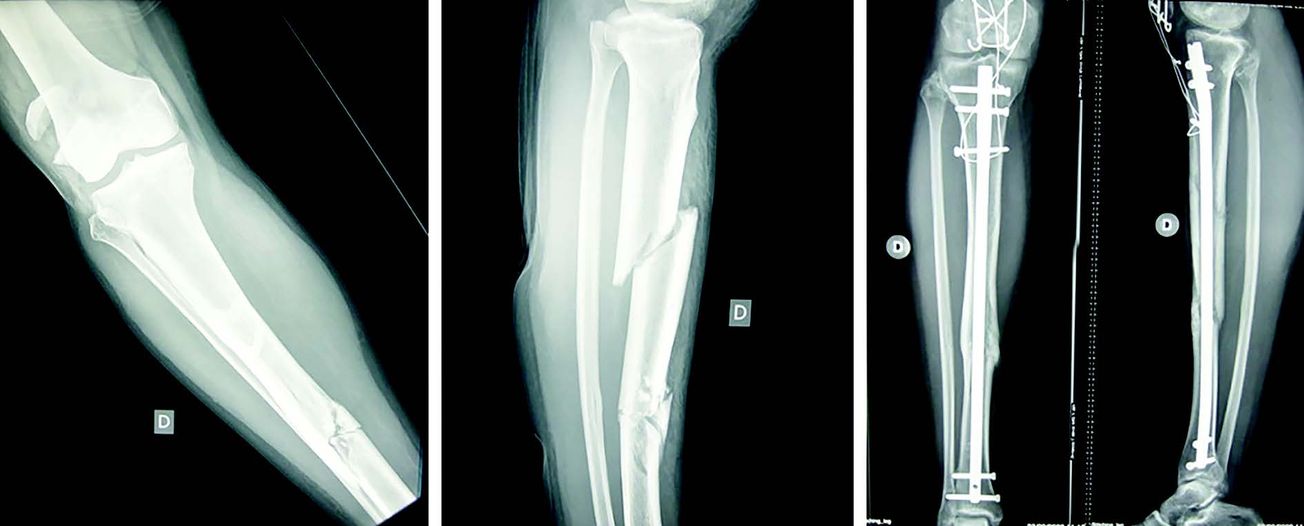

Mise au point Enclouage centromédullaire alésé des os longs du membre inférieur de l’adulte - Principes techniques et données récentes de la littérature , Matthieu Ehlinger Hôpital de Hautepierre, Strasbourg, France 🖂 matthieu.ehlinger@chru-strasbourg.fr , David Brinkert Service de Chirurgie Orthopédique et de Traumatologie, Hôpital de Hautepierre, Hôpitaux Universitaires de Strasbourg, France 1, Avenue Molière, 67098 , Benoit Schenck Service de Chirurgie Orthopédique et de Traumatologie, Hôpital de Hautepierre, Hôpitaux Universitaires de Strasbourg, France 1, Avenue Molière, 67098 , Antonio Di Marco Service de Chirurgie Orthopédique et de Traumatologie, Hôpital de Hautepierre, Hôpitaux Universitaires de Strasbourg, France 1, Avenue Molière, 67098 , Philippe Adam Hôpitaux Universitaires de Strasbourg, Strasbourg, France , Gilbert Taglang Hôpital de Hautepierre, Strasbourg, France , François Bonnomet Hôpital de Hautepierre, Strasbourg, France N°237 - Octobre 2014 ● 33 min de lecture